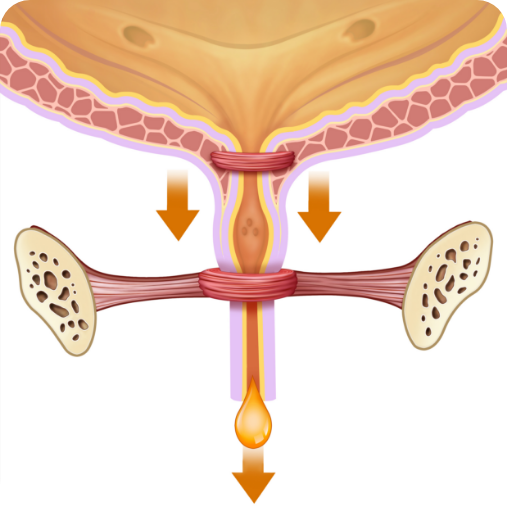

PRED kúrou:

Slabé svaly močovej trubice

PO kúre:

Silné uretrálne svaly